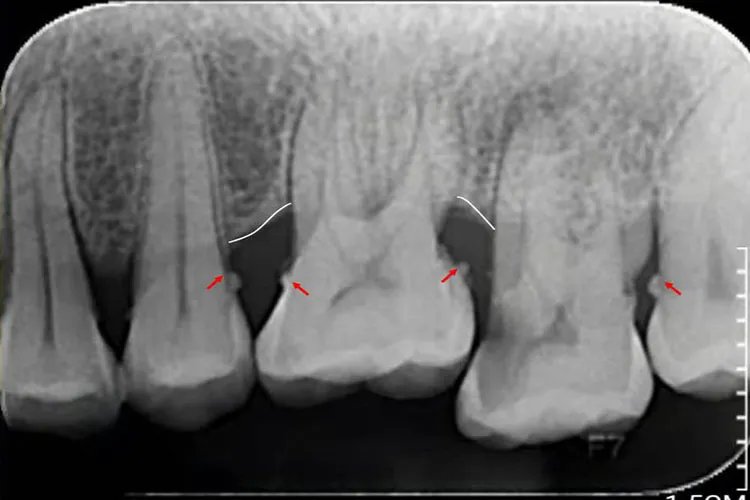

龈下牙结石是指位于龈缘的根方、肉眼不能看到,需要医生用牙科探针才能检查到的牙石。龈下牙石一般颜色较深,呈褐色或黑色,体积较小,质地较坚硬,与牙根表面的附着也较龈上牙石更牢固。龈下牙石在根面的分布较均匀,但一般以邻面较多。